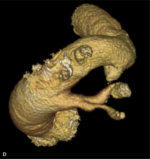

RYCINA. Badanie wykonane 64-rzędowym tomografem komputerowym jednolampowym. Akcja serca podczas badania – 87 uderzeń/min.

Zakres badania – cała klatka piersiowa. [A] Rekonstrukcja VR uwidoczniła prawostronny łuk aorty. [B] Warstwa poprzeczna na poziomie łuku aorty. Widoczne są: niepełny pierścień naczyniowy otaczający tchawicę i przełyk utworzony przez łuk aorty i tętnicę podobojczykową lewą otaczającą tchawicę i przełyk (strzałki). Ściana tętnicy podobojczykowej zawiera blaszki miażdżycowe zwężające jej światło 40%. [C] Warstwa poprzeczna na poziomie nadnercza lewego – widoczny guzek nadnercza lewego (strzałka). [D] Rekonstrukcja VR uwidoczniła prawostronny łuk aorty z częściowym pierścieniem naczyniowym.

Pierścień naczyniowy (rycina D) obejmuje pełną lub częściową obręczą najczęściej przełyk i tchawicę. W obu przypadkach wystąpienie objawów jest identyczne i nie zależy od tego, czy jest to pierścień pełen, czy częściowy.